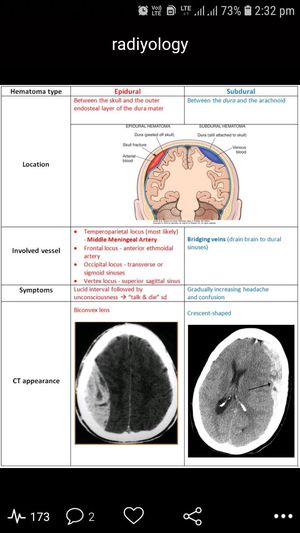

CT brain

Radiology